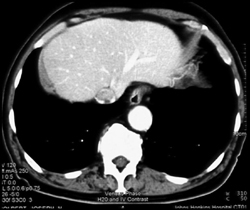

Acute Cholecystitis